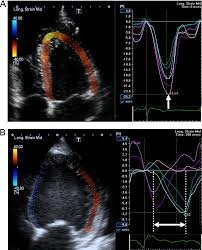

2D and Strain Echocardiography